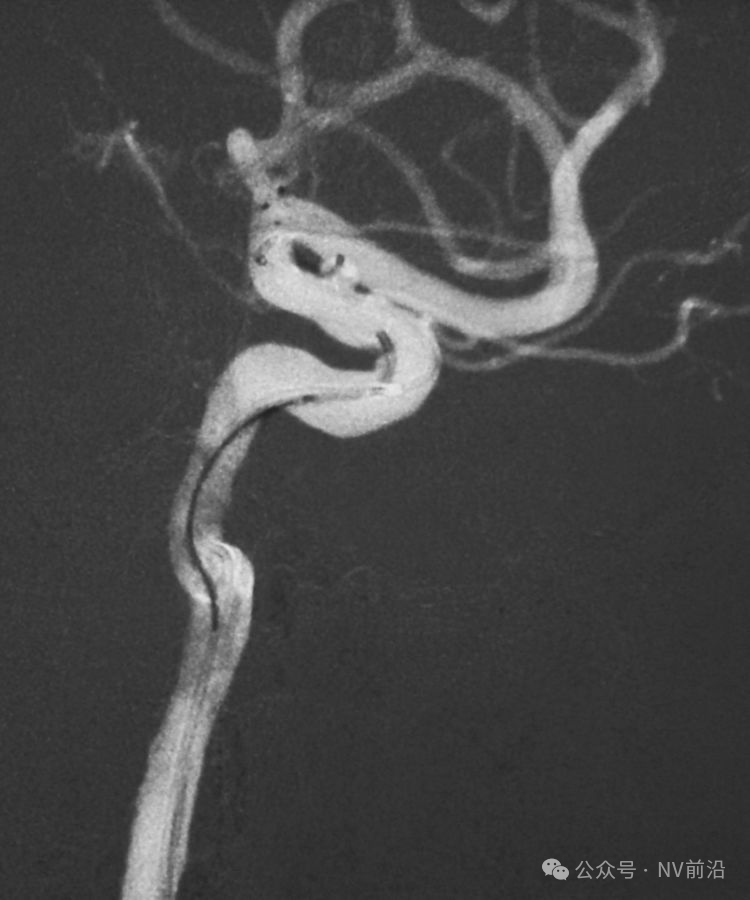

工作位造影

Traxcess 14微导丝可以进入瘤腔,但头端塑成S形的Echelon 10微导管无法跟入。

将微导管在虹吸弯处成襻,越过瘤颈,管头折返钩入瘤腔,即所谓回马枪技术。